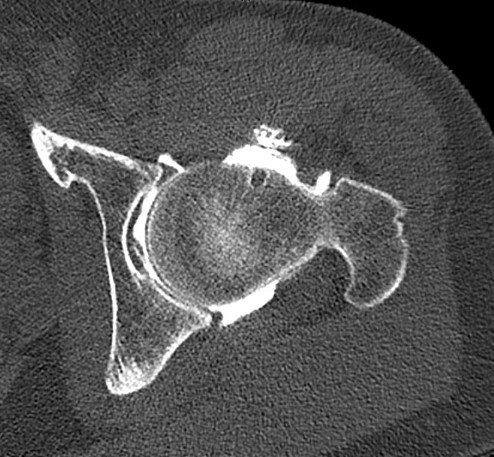

• Male patient 37y

• Chronic left hip pain

• Anterior, exquisite on FADRI

• Intra-articular injection test effective

X-ray: FAI due to CAME effect

ArthroCT: very mild osteoarthritis. Alpha angle > 70°, no labral lesion